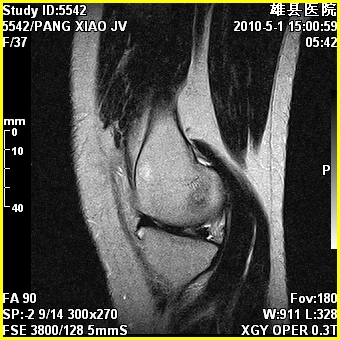

标题: MRI2894:患者右膝关节疼痛两月余,无明显外伤史 [打印本页]

标题: MRI2894:患者右膝关节疼痛两月余,无明显外伤史

右股骨下端前内侧类圆形异常信号,位于干骺端,呈长t1长t2改变,但信号不均,t1图上病灶中心见小片状稍高信号影,t2图上见散在稍低信号影,stir像呈高信号,因病灶较小,缺乏特征性改变,结合患者年龄及部位,考虑嗜酸性肉芽肿可能性大。胫骨关节面下的小囊状异常信号,如果一元论考虑则为嗜酸性肉芽肿,不过发生在这个部位的少见,二元论考虑为邻关节骨囊肿。半月板与前后交叉韧带均未见异常。

考虑---骨囊肿或肉芽肿可能性大。

临关节骨囊肿可优先考虑